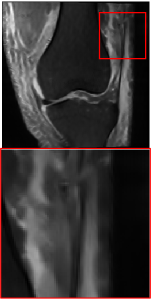

4.3 Qualitative results

Figure 5 provides the qualitative comparison of the various methods on the four datasets at a scale of 4. The top, second, third, and bottom rows are the SR results under the FastMRI, clinical brain, clinical tumor and clinical pelvic datasets, respectively. The red boxes indicate the zoom-in region of complicated anatomical structures along with their corresponding error maps. Note that the brighter textures in the error maps, the lower the quality of the reconstructed images. As can be seen, compared to methods based on Transformers and CNNs, diffusion-based methods like DisC-Diff and DiffMSR (Ours) are capable of reconstructing high-realistic images with promising reconstruction metric scores (PSNR and SSIM). Nevertheless, while DisC-Diff can reconstruct high-precision MR images, it does not preserve the structure present in the original HR images, introducing some additional information that can affect medical diagnosis. In contrast, our method combines DM and PLWformer, which can preserve the original image’s structure while restoring high-frequency information.

9 More Visual Comparisons

In this section, we present more visual qualitative comparisons. Figures 8, 9, 10, and 11 show the reconstruction results of each method in FastMRI, clinical brain, clinical tumor, and clinical pelvic, respectively. As can be seen, although DisC-Diff can reconstruct MR images with high-frequency information, it fails to preserve the structure and content of the original Target HR image effectively, resulting in image distortion. In contrast, our proposed DiffMSR can restore high-frequency information while preserving the structure of the original HR image, indicating the effectiveness of the joint use of DM and PLWformer.